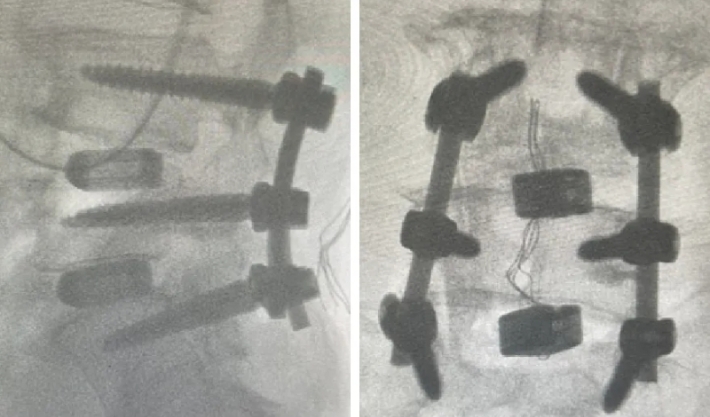

近日,beat365唯一官方网站第六附属医院(新疆维吾尔自治区骨科医院)脊柱外三科在医疗技术上取得新的突破,成功为两位腰椎手术患者利用3D打印融合器实施了腰椎椎体间融合术,患者术后恢复良好。

随着人口老龄化趋势不断加剧,腰椎间盘突出症、腰椎管狭窄症、腰椎滑脱等已成为常见的退行性脊柱疾病之一,严重影响中老年人的生活质量和身心健康。腰椎椎体间融合术是解决退行性脊柱疾病的常用手术方式之一。然而,在老年人骨质疏松、骨含量低的情况下,容易发生植骨融合失败的后遗症。3D打印融合器能有效解决这一问题。这两例手术中所使用的融合器,是通过3D打印技术制造的一种新型的多孔钛合金椎间融合器,它的微观和宏观结构模仿了人体椎体的天然骨小梁,更加贴合人体结构。同时,进一步优化了材料表面,使其具有更好的生物相容性和成骨活性,能够帮助新生骨快速长入融合器,加速愈合。该融合器还很适合微创手术,不需要再植入自体骨或其他骨修复材料,不仅提高了治疗效果,还减少了患者的手术创伤。

随着3D打印技术的不断成熟,这一技术有望在更多脊柱疾病治疗中推广应用。作为全疆最先运用3D打印脊柱椎间融合器的科室,该院脊柱外三科将继续紧跟时代步伐,积极应用数字化辅助技术和医工结合技术,致力于实现个体化、精准化的治疗,为患者带来更加安全、高效、舒适的医疗服务体验。